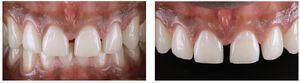

Figs. 2a a 2c. La situación antes de la operación presenta deficiencias en las proporciones de anchura y longitud de los incisivos centrales superiores, diastemas y una ligera sonrisa gingival.

Figs. 9a a 9c. La situación 90 días después de la intervención quirúrgica y un blanqueamiento de dos semanas en casa. El recorrido gingival sigue la línea labial inferior y ya no se aprecia sonrisa gingival

Figs. 10a y 10b. El nuevo recorrido gingival.